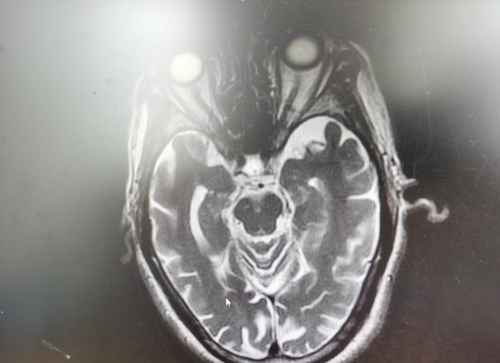

朱爷爷今年92岁,于2月18日晚饭后无明显诱因出现头晕、恶心、伴视物旋转、吐字不清、行走不稳急送武汉大医院。行颅脑影像学检查提示:多发性腔梗、脑萎缩。经临床治疗病情稳定,但仍遗留吞咽困难,滴水难进问题。为进一步解决吞咽困难问题,患者于3月5日求医至江西省人民医院康复医学科。

2月18日的颅脑影像

患者脑梗在桥脑及延髓的位置,也就是我们所说的脑干部分,而与吞咽主要相关的舌咽神经和迷走神经都分布在那里,若不积极地采取恰当的治疗方法,患者的吞咽功能预后将极差。